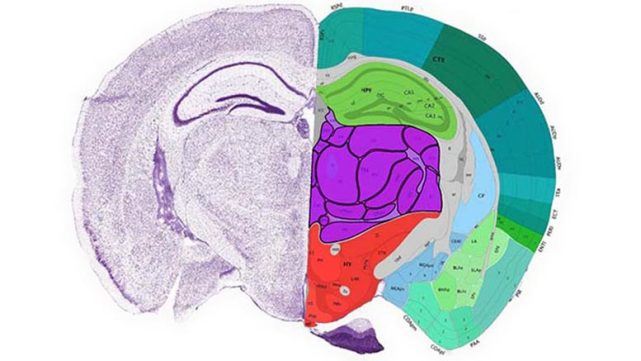

科学家绘制出小鼠大脑图谱为人脑图绘制铺路

图片尺寸641x361